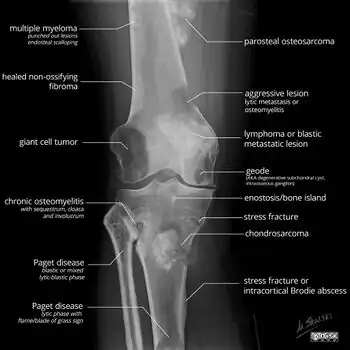

- X-ray appearances of different types of bone tumors in < 30 years.

- X-ray appearances of different types of bone tumors in > 30 years.